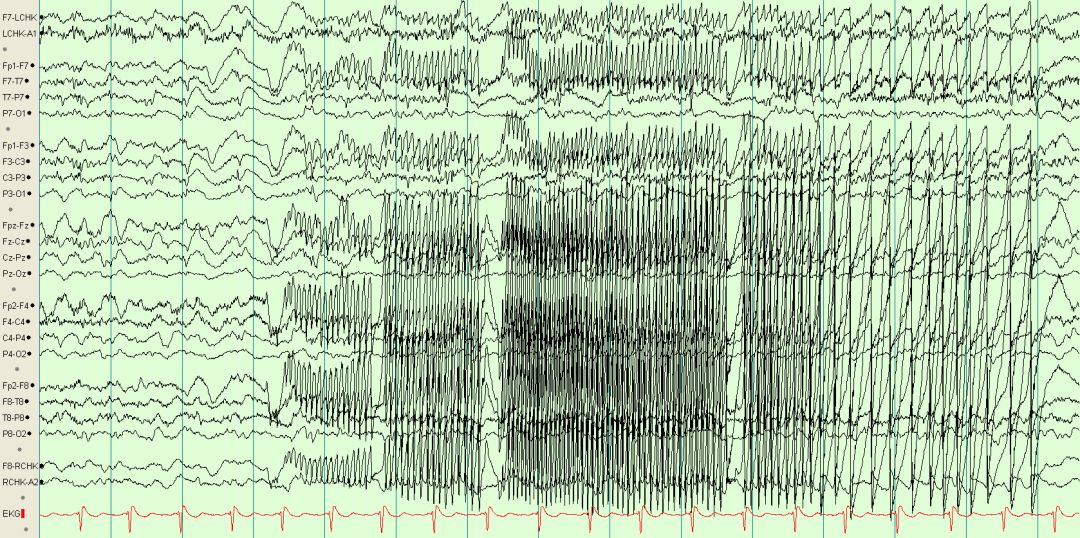

05 运动引起的伪差

患者在检查期间主动或被动运动可引起不同形式的伪差,造成伪差的原因是多方面的,包括电极的移动、导线摆动、静电干扰、肌电伪差等多种因素(见图4-1、4-2、4-3、4-4、4-5、4-6、4-7、4-8、4-9、4-10)。

未标注脑电图 图4-1

标注脑电图 图4-2随机运动引起的伪差

未标注脑电图 图4-3

标注脑电图 图4-4 不明原因节律性运动伪差

节律性运动或活动造成导联线节律性摆动引起的伪差,类似广泛性尖波节律。